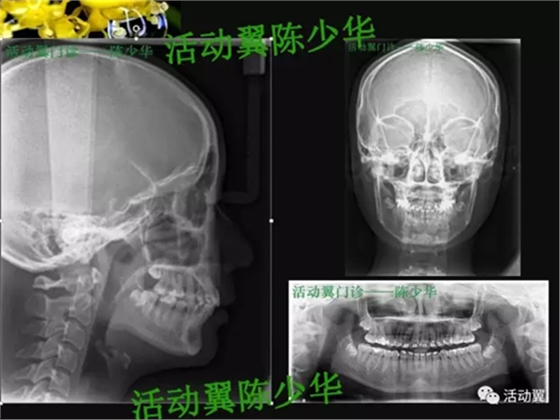

•主訴:上牙前突,上下牙不齊,要求矯正。•牙列檢查:年輕恒牙17-27、37-47。磨牙尖牙遠(yuǎn)中關(guān)系;前牙覆蓋6MM,深覆合2度,上牙前傾,下前牙輕度擁擠,Spee曲深。•面型:直面型。下頜輕度后縮。上下頜骨突度正常。顳下頜功能檢查未發(fā)現(xiàn)明顯異常。